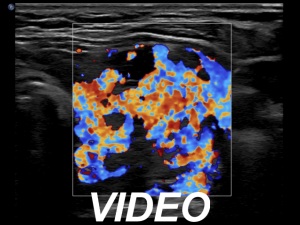

First examination (first row of images):

Clinical presentation: A 54-year-old woman was referred for an evaluation of complaints suggesting hyperthyroidism. She was treated with Graves' disease 16 years ago.

Palpation: Both lobes were enlarged and moderately firm.

Results of blood tests: hyperthyroidism (TSH undetectable, FT4 33.1 pM/L).

Ultrasonography. The thyroid was moderately hypoechoic. There was a more hypoechoic lesion in the central part of the lobe. The lesion was avascular.Aspiration cytology of the lesion resulted in benign hormonal atypia.

Thyrostatic therapy was started.